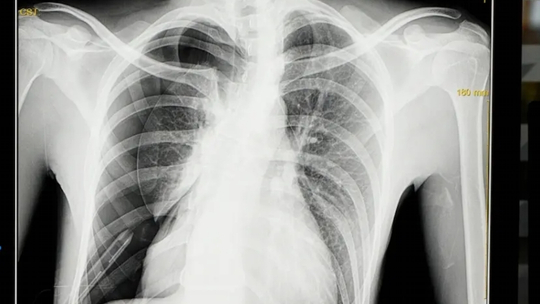

Gambar 1. Gambaran foto toraks pada pasien pneumotoraks sekunder akibat TB paru menggambarkan adanya pneumotoraks di sebelah kanan bawah paru dengan luas menurut kriteria Light sebesar >20%, infiltrat yang sudah menyebar luas di paru kanan dan paru kiri bawah.